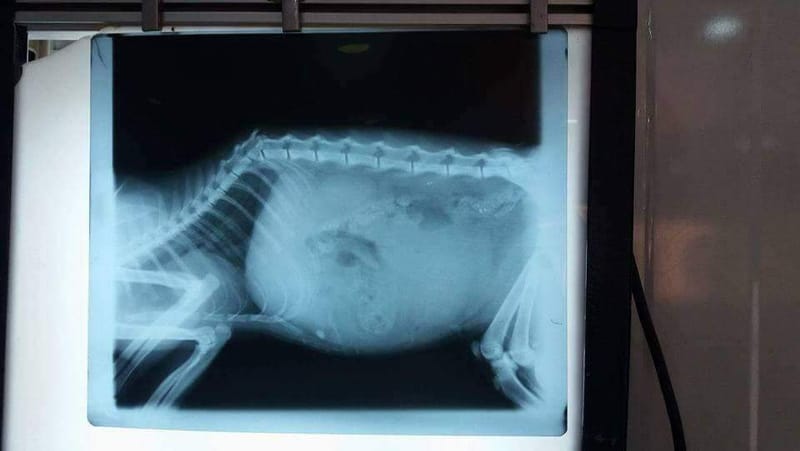

كسر في العامود الفقري

لقد تعرض هذا القط الى حاله دهس مما ادى الى تكسر العامود الفقري ولقد كانت من العمليات الكبرى

ولقد استغرقت 6 ساعات لكي يتم اعاده العامود الفقري بنجاح مع مراعاه الحبل الشوكي الذي بدوره يكون داخل العامود  الفقري الفضل كله الى البروفسور د.حميد علي  التميمي